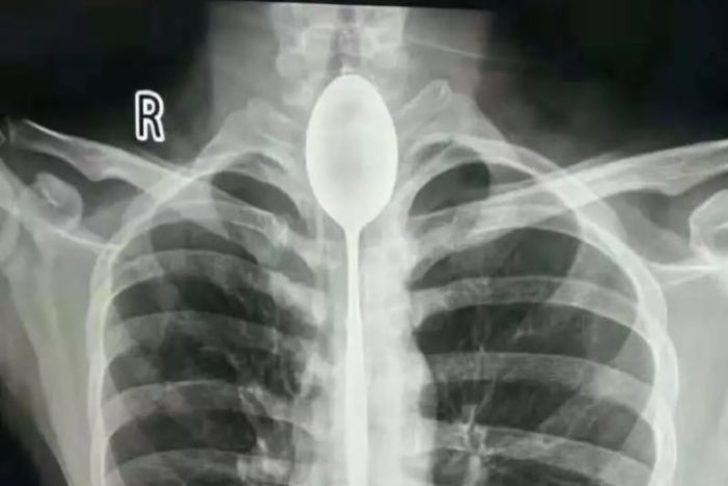

Metbuat.az xarici KİV-ə istinadla bildirir ki, Zanq adlı şəxs nəfəs almaqda çətinlik çəkdiyi üçün xəstəxanaya aparılıb. Həkim müayinəsi nəticəsində onun boğazında qaşıq tapılıb və dərhal əməliyyata alınıb.

Məlum olub ki, gənc oğlan "gücünü" göstərmək üçün 20 santimetr uzunluğunda qaşıq udub. Zanq bir müddət bu formada normal həyatını yaşayıb. Ancaq bir gün sinəsindən alan yumruq nəticəsində nəfəs almağı çətinləşib və həkimə müraciət etməli olub.

Həkimlərin sözlərinə görə, əməliyyat olduqca çətin keçib. 2 saat çəkən əməliyyatla qaşıq Zanqın boğazından çıxarılıb.